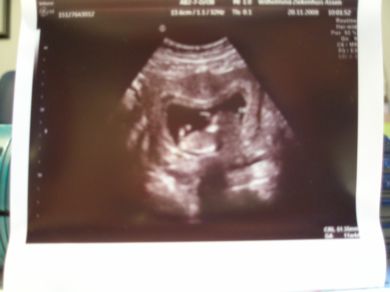

Echo foto's van Judith

Hier zijn ze dan, wel scans maar toch duidelijk te zien

een nieuw leventje in je buik blijft toch een wonder